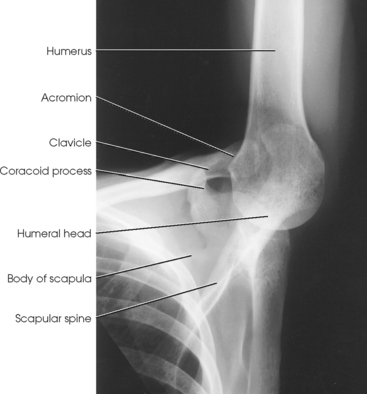

The proximal end of the humerus consists of a head, an anatomic neck, two prominent processes called the greater and lesser tubercles, and the surgical neck (Fig. 5-5). The head is large, smooth, and rounded, and it lies in an oblique plane on the superomedial side of the humerus. Just below the head, lying in the same oblique plane, is the narrow, constricted anatomic neck. The constriction of the body just below the tubercles is called the surgical neck, which is the site of many fractures.

The lesser tubercle is situated on the anterior surface of the bone, immediately below the anatomic neck (Figs. 5-6 and 5-7; see Fig. 5-5). The tendon of the subscapular muscle inserts at the lesser tubercle. The greater tubercle is located on the lateral surface of the bone, just below the anatomic neck, and is separated from the lesser tubercle by a deep depression called the intertubercular (bicipital) groove. The superior surface of the greater tubercle slopes posteriorly at an angle of approximately 25 degrees and has three flattened impressions for muscle insertions. The anterior impression is the highest of the three and affords attachment to the tendon of the supraspinatus muscle. The middle impression is the point of insertion of the infraspinatus muscle. The tendon of the upper fibers of the teres minor muscle inserts at the posterior impression (the lower fibers insert into the body of the bone immediately below this point).

The scapulohumeral articulation between the glenoid cavity and the head of the humerus forms a synovial ball-and-socket joint, allowing movement in all directions (Figs. 5-9 and 5-10). This joint is often referred to as the glenohumeral joint. Although many muscles connect with, support, and enter into the function of the shoulder joint, radiographers are chiefly concerned with the insertion points of the short rotator cuff muscles (Fig. 5-11). The insertion points of these muscles—the subscapular, supraspinatus, infraspinatus, and teres minor—have already been described.